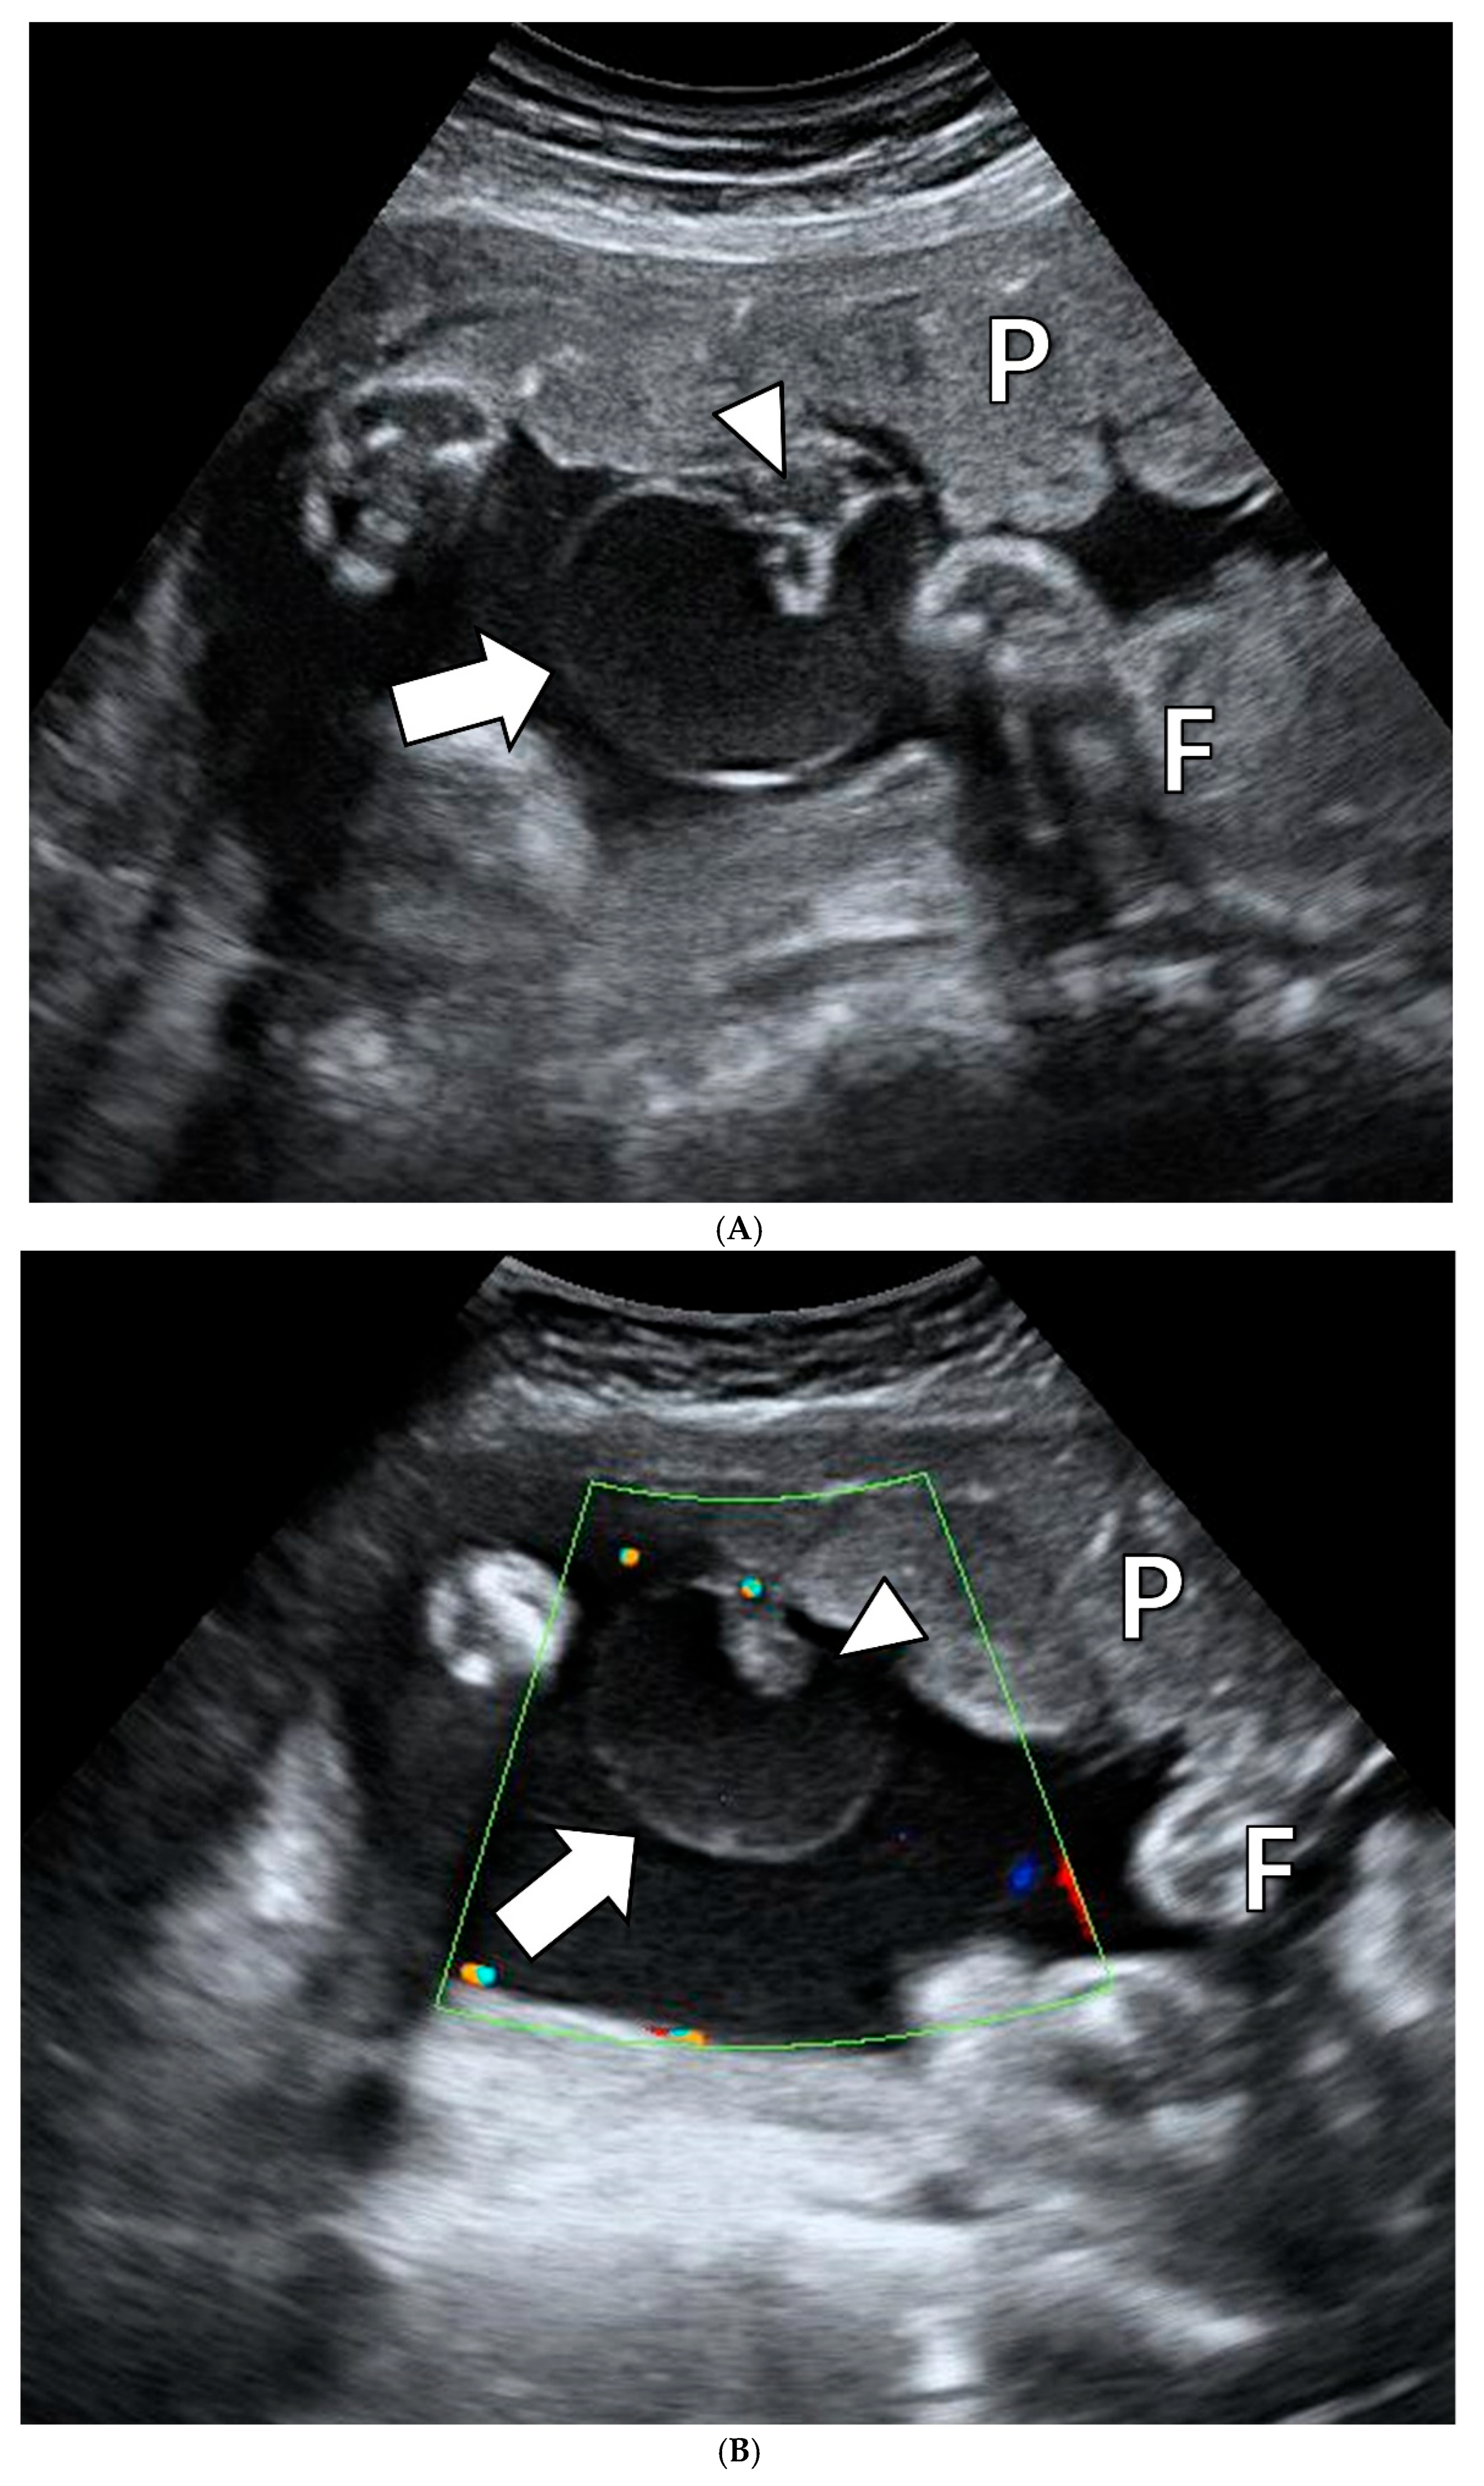

2.1. Clinical Presentation